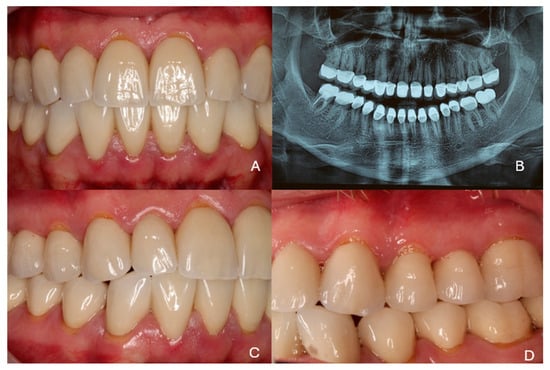

2. Case Presentation